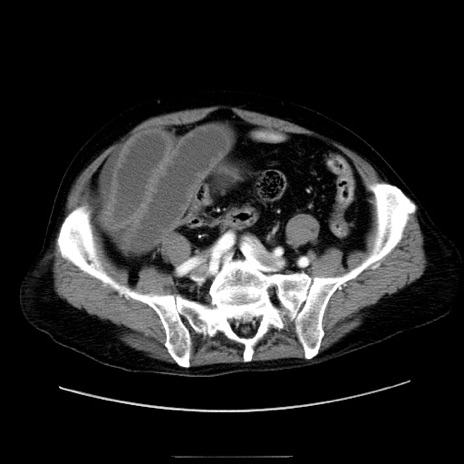

症例30(横断像)

【症例】80歳代男性

【主訴】臍周囲痛

【現病歴】約6時間前から臍下部痛が出現。次第に腹部膨隆・背部痛も生じてきたため来院。背部痛の場所は変化しない。

【身体所見】意識清明、BT 36.3℃、BP  131/87mmHg、P 87bpm、SpO2 100%(RA)、臍周囲自発痛・圧痛あり、反跳痛なし、自発痛部位に一致して板状硬あり、腹部膨隆、腸雑音減弱、CVA tenderness両側陰性。

【データ】WBC 19600、CRP 0.33